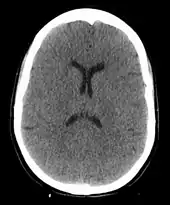

The cause of death in hanging depends on the conditions related to the event. When the body is released from a relatively high position, the major cause of death is severe trauma to the upper cervical spine. The injuries produced are highly variable. One study showed that only a small minority of a series of judicial hangings produced fractures to the cervical spine (6 out of 34 cases studied), with half of these fractures (3 out of 34) being the classic "hangman's fracture" (bilateral fractures of the pars interarticularis of the C2 vertebra).[26] The location of the knot of the hanging rope is a major factor in determining the mechanics of cervical spine injury, with a submental knot (hangman's knot under the chin) being the only location capable of producing the sudden, straightforward hyperextension injury that causes the classic "hangman's fracture".

The side, or subaural knot, has been shown to produce other, more complex injuries, with one thoroughly studied case producing only ligamentous injuries to the cervical spine and bilateral vertebral artery disruptions, but no major vertebral fractures or crush injuries to the spinal cord.[27] Death from a "hangman's fracture" occurs mainly when the applied force is severe enough to also cause a severe subluxation of the C2 and C3 vertebra that crushes the spinal cord and/or disrupts the vertebral arteries. Hangman's fractures from other hyperextension injuries (the most common being unrestrained motor vehicle accidents and falls or diving injuries where the face or chin suddenly strike an immovable object) are frequently survivable if the applied force does not cause a severe subluxation of C2 on C3.

In the absence of fracture and dislocation, occlusion of blood vessels becomes the major cause of death, rather than asphyxiation. Obstruction of venous drainage of the brain via occlusion of the internal jugular veins leads to cerebral oedema and then cerebral ischemia. The face will typically become engorged and cyanotic (turned blue through lack of oxygen). There will be the classic sign of strangulation, petechiae, little blood marks on the face and in the eyes from burst blood capillaries. The tongue may protrude.

Compromise of the cerebral blood flow may occur by obstruction of the carotid arteries, even though their obstruction requires far more force than the obstruction of jugular veins, since they are seated deeper and they contain blood in much higher pressure compared to the jugular veins. Where death has occurred through carotid artery obstruction or cervical fracture, the face will typically be pale in colour and not show petechiae. Many reports and pictures exist of actual short-drop hangings that seem to show that the person died quickly, while others indicate a slow and agonising death by strangulation.[28]

When cerebral circulation is severely compromised by any mechanism, arterial or venous, death occurs over four or more minutes from cerebral hypoxia, although the heart may continue to beat for some period after the brain can no longer be resuscitated. The time of death in such cases is a matter of convention. In judicial hangings, death is pronounced at cardiac arrest, which may occur at times from several minutes up to 15 minutes or longer after hanging. During suspension, once the prisoner has lapsed into unconsciousness, rippling movements of the body and limbs may occur for some time which are usually attributed to nervous and muscular reflexes. In Britain, it was normal to leave the body suspended for an hour to ensure death.